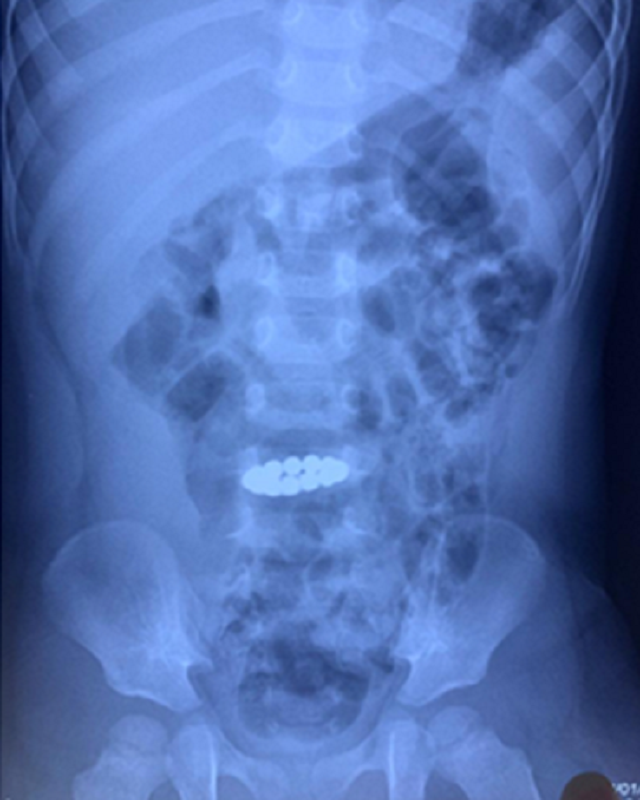

Chuỗi nam châm hít vào nhau được phát hiện trên hình ảnh X-quang bụng của bệnh nhi.

Tuy nhiên, một tháng sau trẻ đột nhiên bị đau bụng, tình trạng diễn tiến nặng phải chuyển đến Bệnh viện Nhi Đồng cấp cứu. Các bác sỹ kiểm tra hình ảnh và phát hiện dị vật còn trong đường ruột của bệnh nhi và hít vào nhau xếp thành hình vòng tròn.